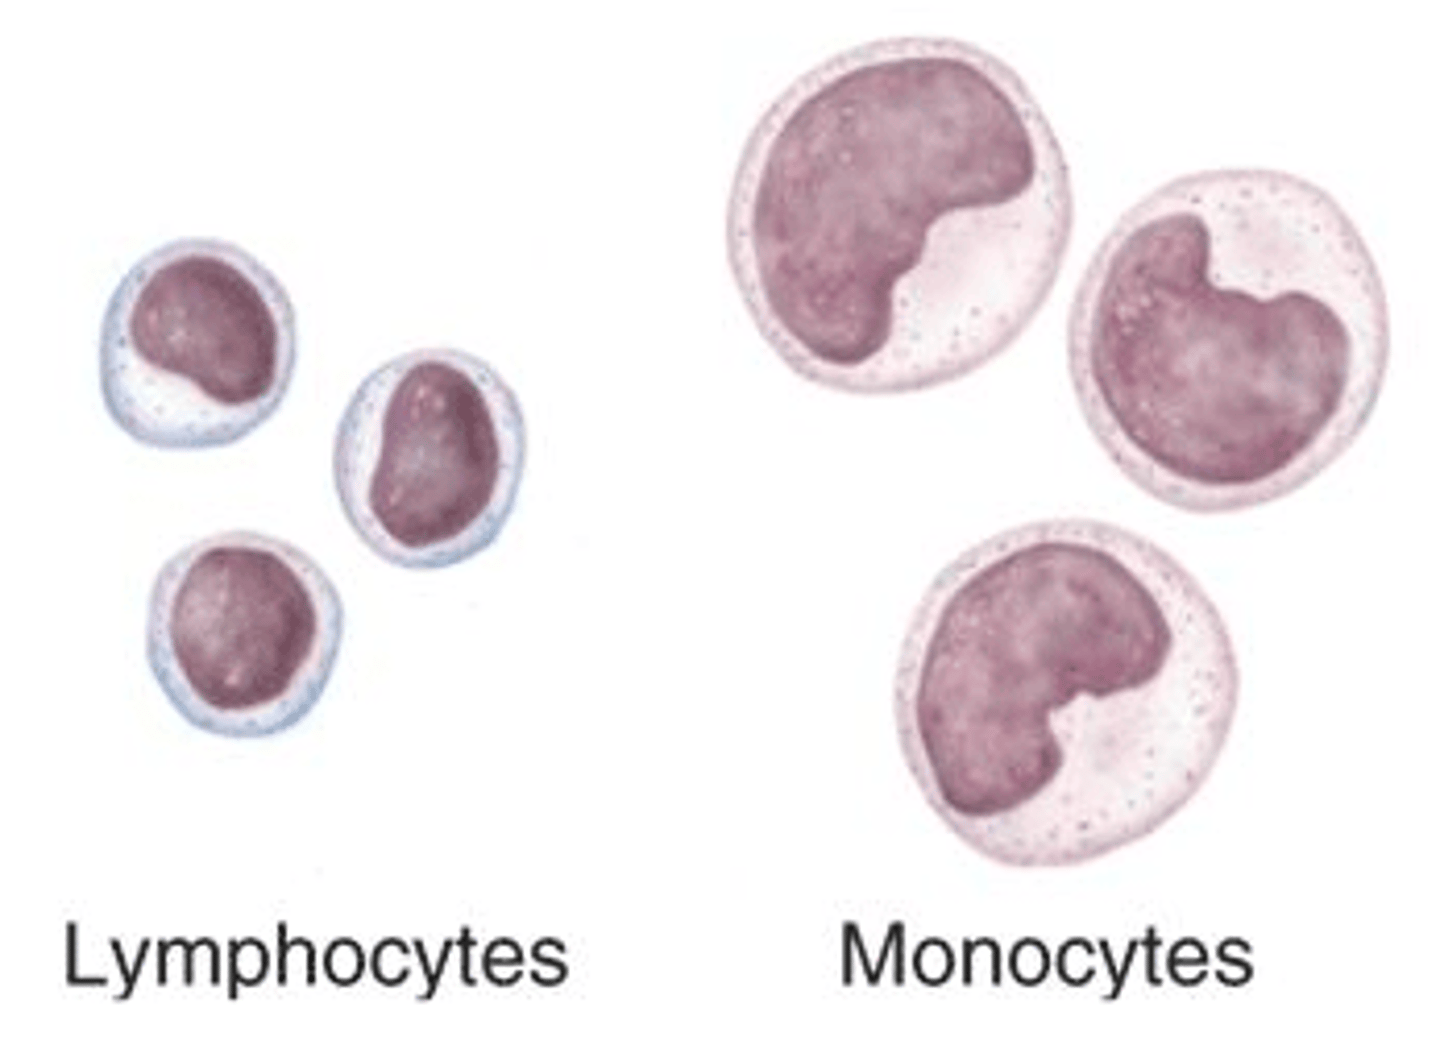

Agranular leukocytes

Lymphocytes and monocytes

No granules

What is unique about lymphocytes?

They can move between blood and lymphatic tissue, whereas all others only circulate in blood

That's why they're called LYMPHocytes you silly goose

Monocytes

Structure: Largest WBCs, U shaped nucleus

Function: A large WBC that transform into macrophages to fight off viruses and chronic infections

Lymphocytes

Structure: Has a large, dark purple nucleus that takes up most of the cell volume

Function: B cells make antibodies, T cells fight off viral infections, NK cells